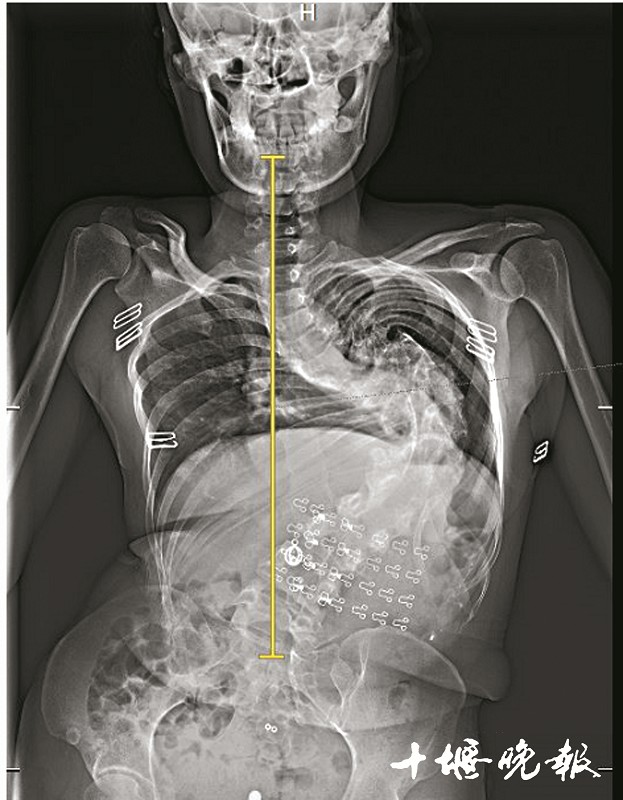

王欣手术前的X光片。

脊柱在胸后背拐了道90度的弯,并向后凸60度,后背隆起,身形扭曲,身高仅1.4米……过去30年,王欣(化名)始终无法面对这样“畸形”的自己,也没少遭人异样眼光。更可怕的是,由于脊柱严重侧弯,致使她的肺、胃等脏器受到挤压,呼吸和消化系统也受到影响。

经检查,王欣确诊为脊柱重度僵硬性侧后凸。其中,脊柱侧弯达90度,后凸达60度。从后背看,她的脊柱扭曲得像麻花。

据王达义介绍,脊柱侧弯分为先天性和后天性。其中,先天性为骨骼生长不全所致,即该长的骨头没有长出来;后发性通常单个椎骨都是好的,只不过序列是歪的,王欣便属于该类型。因现代医学科学还没搞清楚病因,故也称之为特发性脊柱侧弯。“侧弯如此严重,在业内属于高难度手术。”王达义说,他们先对王欣进行了一个多星期的适当牵引。结果显示,王欣的脊柱弯曲仅稍有缓解,属于僵硬性畸形。为此,他们制订了大范围截骨矫形的手术方案。

5个小时的手术很成功。两次手术,王欣先后共截除脊椎骨3节、肋骨4节。术后评估显示,王欣原本侧弯90度的脊柱,纠正了近80%,后凸畸形100%矫正。当她站立走路时,外观已和常人无异。术后,她的身高也由原来的1.4米增加到1.52米,比她丈夫还要高。